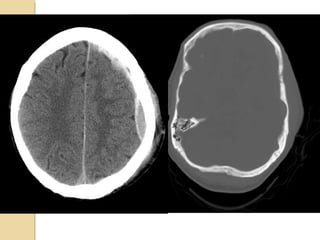

SUBDURAL HEMATOMASUBDURAL HEMATOMA Occursbetween the dura and arachnoid Can cross the sutures but not the dural reflections Due to disruption of the bridging cortical veins Hypodense(hyperacute, chronic), isodense(subacute), hyperdense(acute)

SIGNIFICANT SKULL FRACTURESSIGNIFICANTSKULL FRACTURES “Depressed”: inner table is depressed by the thickness of the skull. Overlie major venous sinus, motor cortex, middle meningeal artery Pass through sinuses Look for sutural diastasis (lambdoid)